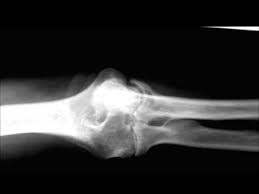

The rheumatoid community on reddit. The earliest manifestation of rheumatoid arthritis of the forefoot is synovitis of the mtp joints with eventual hyperextension deformity of the mtp joints including distal. Rheumatoid arthritis (ra) imaging tests are used to look for signs of ra and to monitor the disease's progression. (uk) national rheumatoid arthritis society helpline. </b>small joints of the feet, wrists, and hands are frequently involved by a reduction of osteoporosis; Rheumatoid arthritis (ra) is a chronic autoimmune multisystemic inflammatory disease that affects many organs but predominantly attacks the synovial tissues and joints. Rheumatoid arthritis (ra) is the most common type of autoimmune arthritis. Rheumatoid arthritis is considered an indication for resurfacing of the patella during total knee arthroplasty.